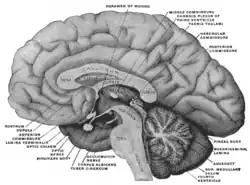

Mesal aspect of a brain sectioned in the median sagittal plane.

Mesal aspect of a brain sectioned in the median sagittal plane. The fornix and corpus callosum from below.

The fornix and corpus callosum from below.